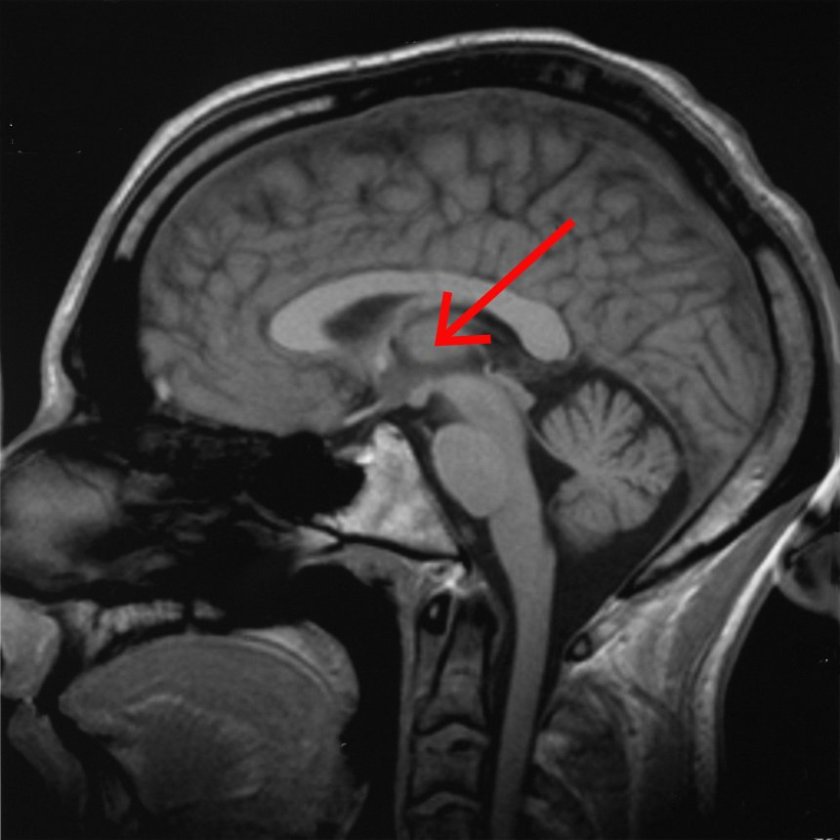

在发表在《神经元》杂志上的一项研究中,威斯康星大学麦迪逊分校的研究人员表明,频率为50 Hz时,中央外侧丘脑的电刺激能够使处于麻醉状态的猕猴苏醒并引发正常的清醒行为。

长期以来,科学家一直在研究位于大脑深处脑干附近的丘脑,以了解丘脑在睡眠、苏醒、意识和机敏性中起什么作用。但是这项针对特定区域应用电刺激的研究使搜索范围比以往任何时候都缩小了。研究中使用的电极更适合他们设计要工作的大脑结构的形状,电刺激旨在模仿正常的醒来的大脑的活动。

研究人员以猕猴为动物模型。通过研究清醒、睡眠和麻醉的动物,他们能够将意识中涉及的大脑区域缩小到比其他研究更为具体的区域。他们还能够排除先前意识相关的神经相关研究中提出的某些领域。他们最终集中在前脑深处的中央外侧丘脑。